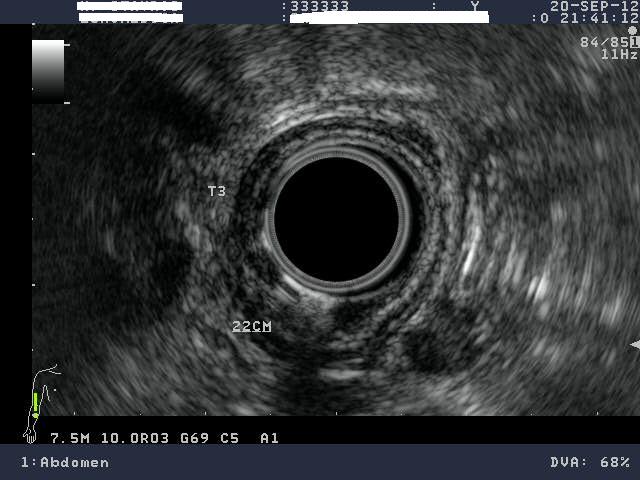

Με τη βοήθεια ειδικού ενδοσκοπίου, που εκτός από την οπτική κάμερα, φέρει στο άκρο του μια κεφαλή υπερήχων, διενεργείται υπέρηχος στα όργανα της κοιλιακής χώρας, μέσα από τον οισοφάγο, τον στόμαχο ή το παχύ έντερο. Επειδή η κεφαλή του υπερήχου είναι σε άμεση επαφή με το όργανο του σώματος που εξετάζεται, η διακριτική ικανότητα του ενδοσκοπικού υπερήχου είναι πολύ υψηλή. Μέσα από το κανάλι του ενδοσκοπίου μπορεί να περάσει λεπτή βελόνα με την οποία λαμβάνονται «βαθιές» βιοψίες από το τοίχωμα του στομάχου ή του εντέρου, αλλά και από γειτονικά όργανα (πάγκρεας, λεμφαδένες).

•    Σε ασθενείς με καρκίνο οισοφάγου, στομάχου, παγκρέατος, χοληφόρων και ορθού για να διαπιστωθεί το «βάθος» διήθησης του τοιχώματος από τη νόσο, καθώς και η επέκταση στους τοπικούς λεμφαδένες, πριν από την έναρξη θεραπείας.